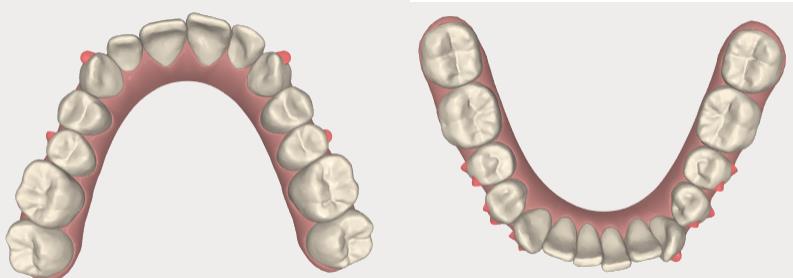

Methods: The clinical examination included extra-oral and intra-oral photographs, panoramic radiographic, lateral cephalometric, stone casts, and upper and lower arch analysis obtained from ClinCheck 3.0.The treatment planning was resolved the crowding in both upper and lower arches and the severe rotation of 33 tooth (46°) using Invisalign system as well as the canine and molar relationship, dental verticalization, adequate over jet, overbite and dental midline using the same system. The duration of the treatment was approximately eight months.

Results: In Post-treatment extra oralphotographs, no significant changes were observed at the end of the treatment. Intraoral photographs showed an important and notable improved aesthetics. The canine relationship improved slightly and molar Class Irelationship was maintained. An increase in transverse diameter was observed at the level of first premolars, second premolars and first molars. The overbite was improved. The crowding and the severe canine rotation were corrected. No obvious root resorption was radiographically evident and slight cephalometric changes.